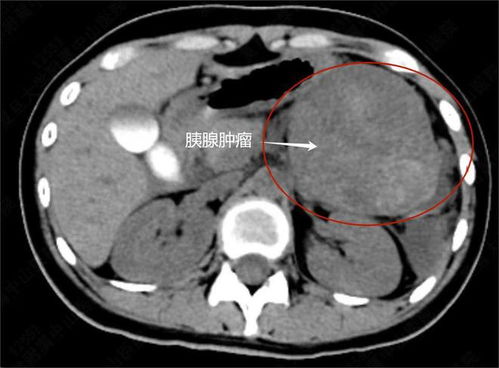

这位女子名叫小芳(化名),她原本是一个健康、活泼的年轻女性,在某一天,她突然感到身体不适,经过一系列的检查和诊断,她被确诊为患有一种恶性肿瘤,这个消息对于她来说是一个巨大的打击,但她并没有放弃,而是选择了勇敢地面对。

在得知自己的病情后,小芳开始了漫长的治疗过程,她经历了手术、化疗和放疗等多种治疗方法,尽管她付出了巨大的努力和代价,肿瘤还是在她身上复发了三次,每一次复发都给她带来了巨大的痛苦和困扰,但她始终没有放弃治疗的希望。

除了肿瘤的复发外,小芳还面临着另一个严重的健康问题——腹部积液,由于肿瘤的影响和治疗的副作用,她的腹部积聚了大量的液体,导致她的体重迅速增加,在一段时间内,她的腹部积液竟然达到了近百斤的惊人程度,这不仅给她的身体带来了巨大的负担,也使她的生活陷入了困境。